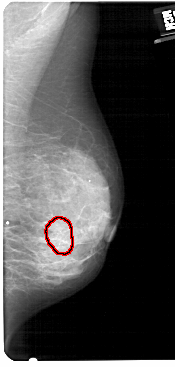

A_1431_1.RIGHT_MLO

LEFT_MLO LINES 5416 PIXELS_PER_LINE 2131 BITS_PER_PIXEL 12 RESOLUTION 43.5 NON_OVERLAY

FILE: A_1431_1.RIGHT_MLO.OVERLAY

TOTAL_ABNORMALITIES 1

ABNORMALITY 1

LESION_TYPE CALCIFICATION TYPE AMORPHOUS DISTRIBUTION CLUSTERED

ASSESSMENT 4

SUBTLETY 3

PATHOLOGY BENIGN

TOTAL_OUTLINES 1

BOUNDARY